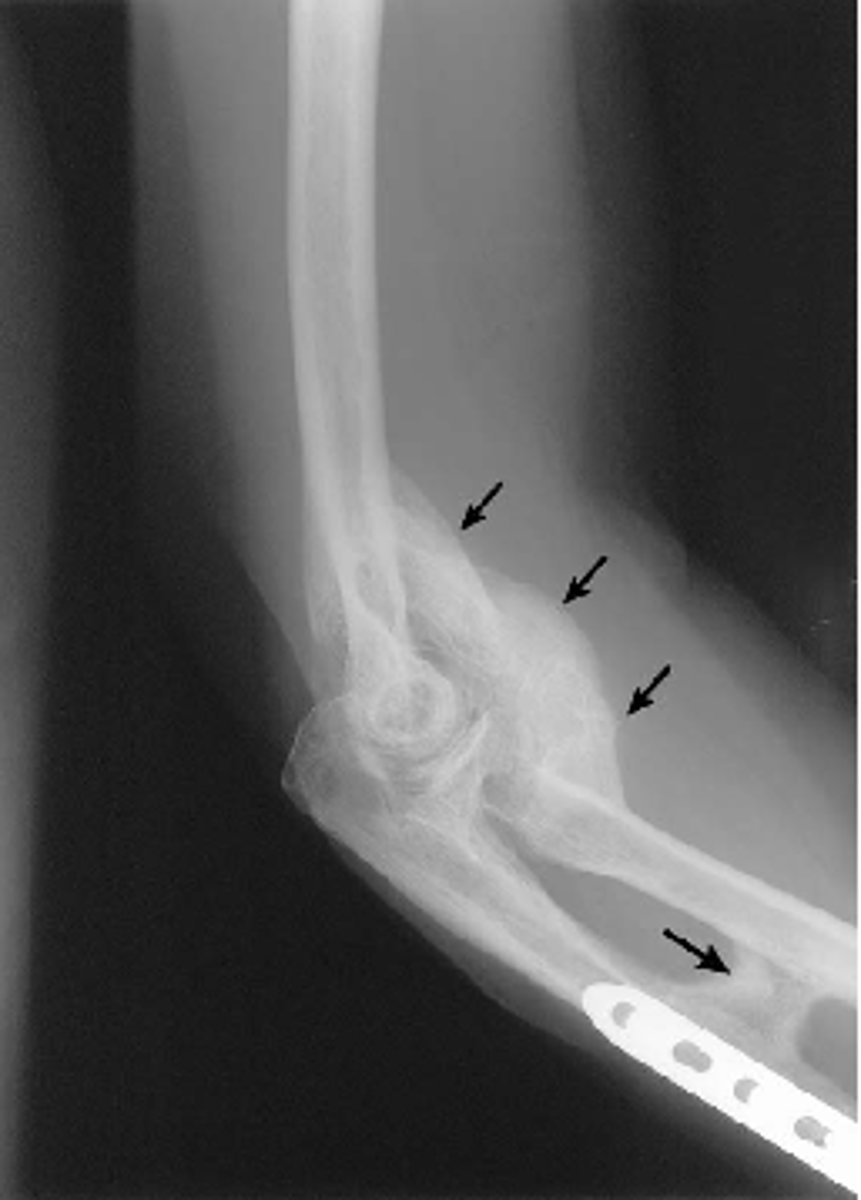

supracondylar fracture

distal humeral fracture

common in kids

typically AIN (branch of median nerve) and brachial artery involvement

complications: volkmanns ischemic contracture, gun stock deformity (reduced carrying angle), high incidence of malunion

requires ORIF